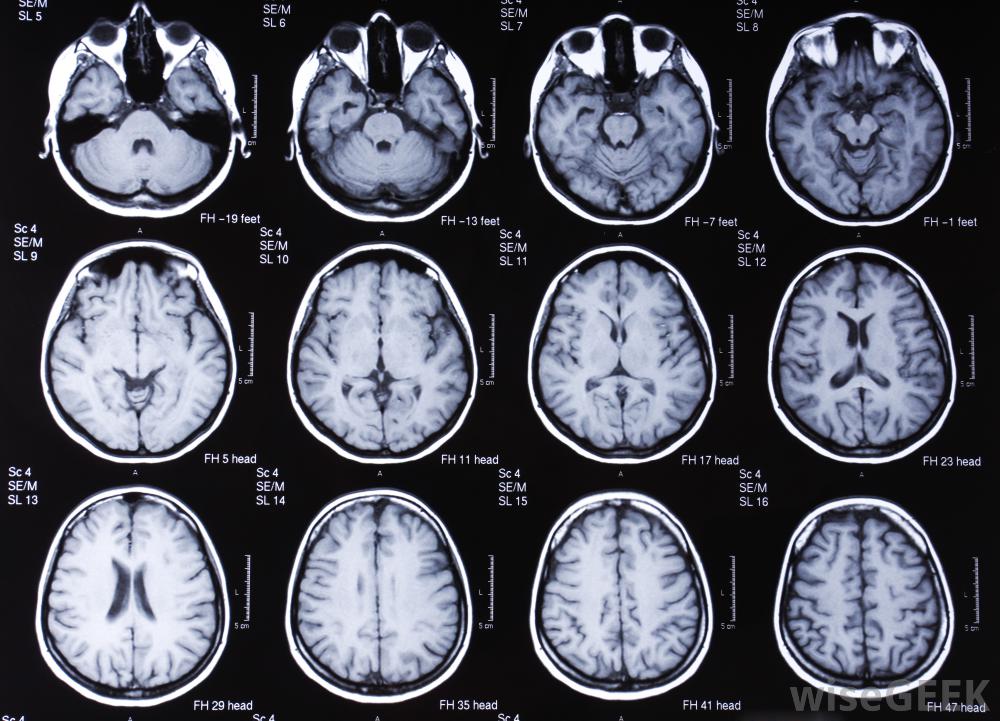

对大脑进行的MRI扫描。MRI和PET扫描都是缩写。MRI是磁共振成像的缩写,PET是正电子发射断层摄影术的意思,虽然这两个词对外行人来说都有点吓人,核磁共振成像仪使用磁场和无线电波来生成内脏和骨骼的图像结构。磁共振成像使用多个磁场,每一个磁场都非常强,以物理方式排列身体内部结构中的特定原子这些磁场使原子中心的原子核旋转运动,这些变化是由于位置的差异以及原子的类型造成的。这些转速的差异被记录下来并转换成磁共振图像。这个图像通常反映了身体的内部结构磁共振成像的优势在于它们能够显示软组织的离散差异,特别是大脑、心脏、肌肉和生长核磁共振成像和PET扫描在形态上有很大的不同。虽然核磁共振成像使用磁场,但一种活性成分是PET扫描成功的关键。这种物质通常被注射到身体的某个特定区域或被摄取,随着这种放射性示踪剂的衰变,它发射带正电的粒子,这些粒子是用专门的设备收集起来的。发射的差异显示了人体系统的工作原理。功能差异可以用计算机图像上不同的亮度和颜色来表示

MRI扫描通常用于诊断损伤或发现异常。